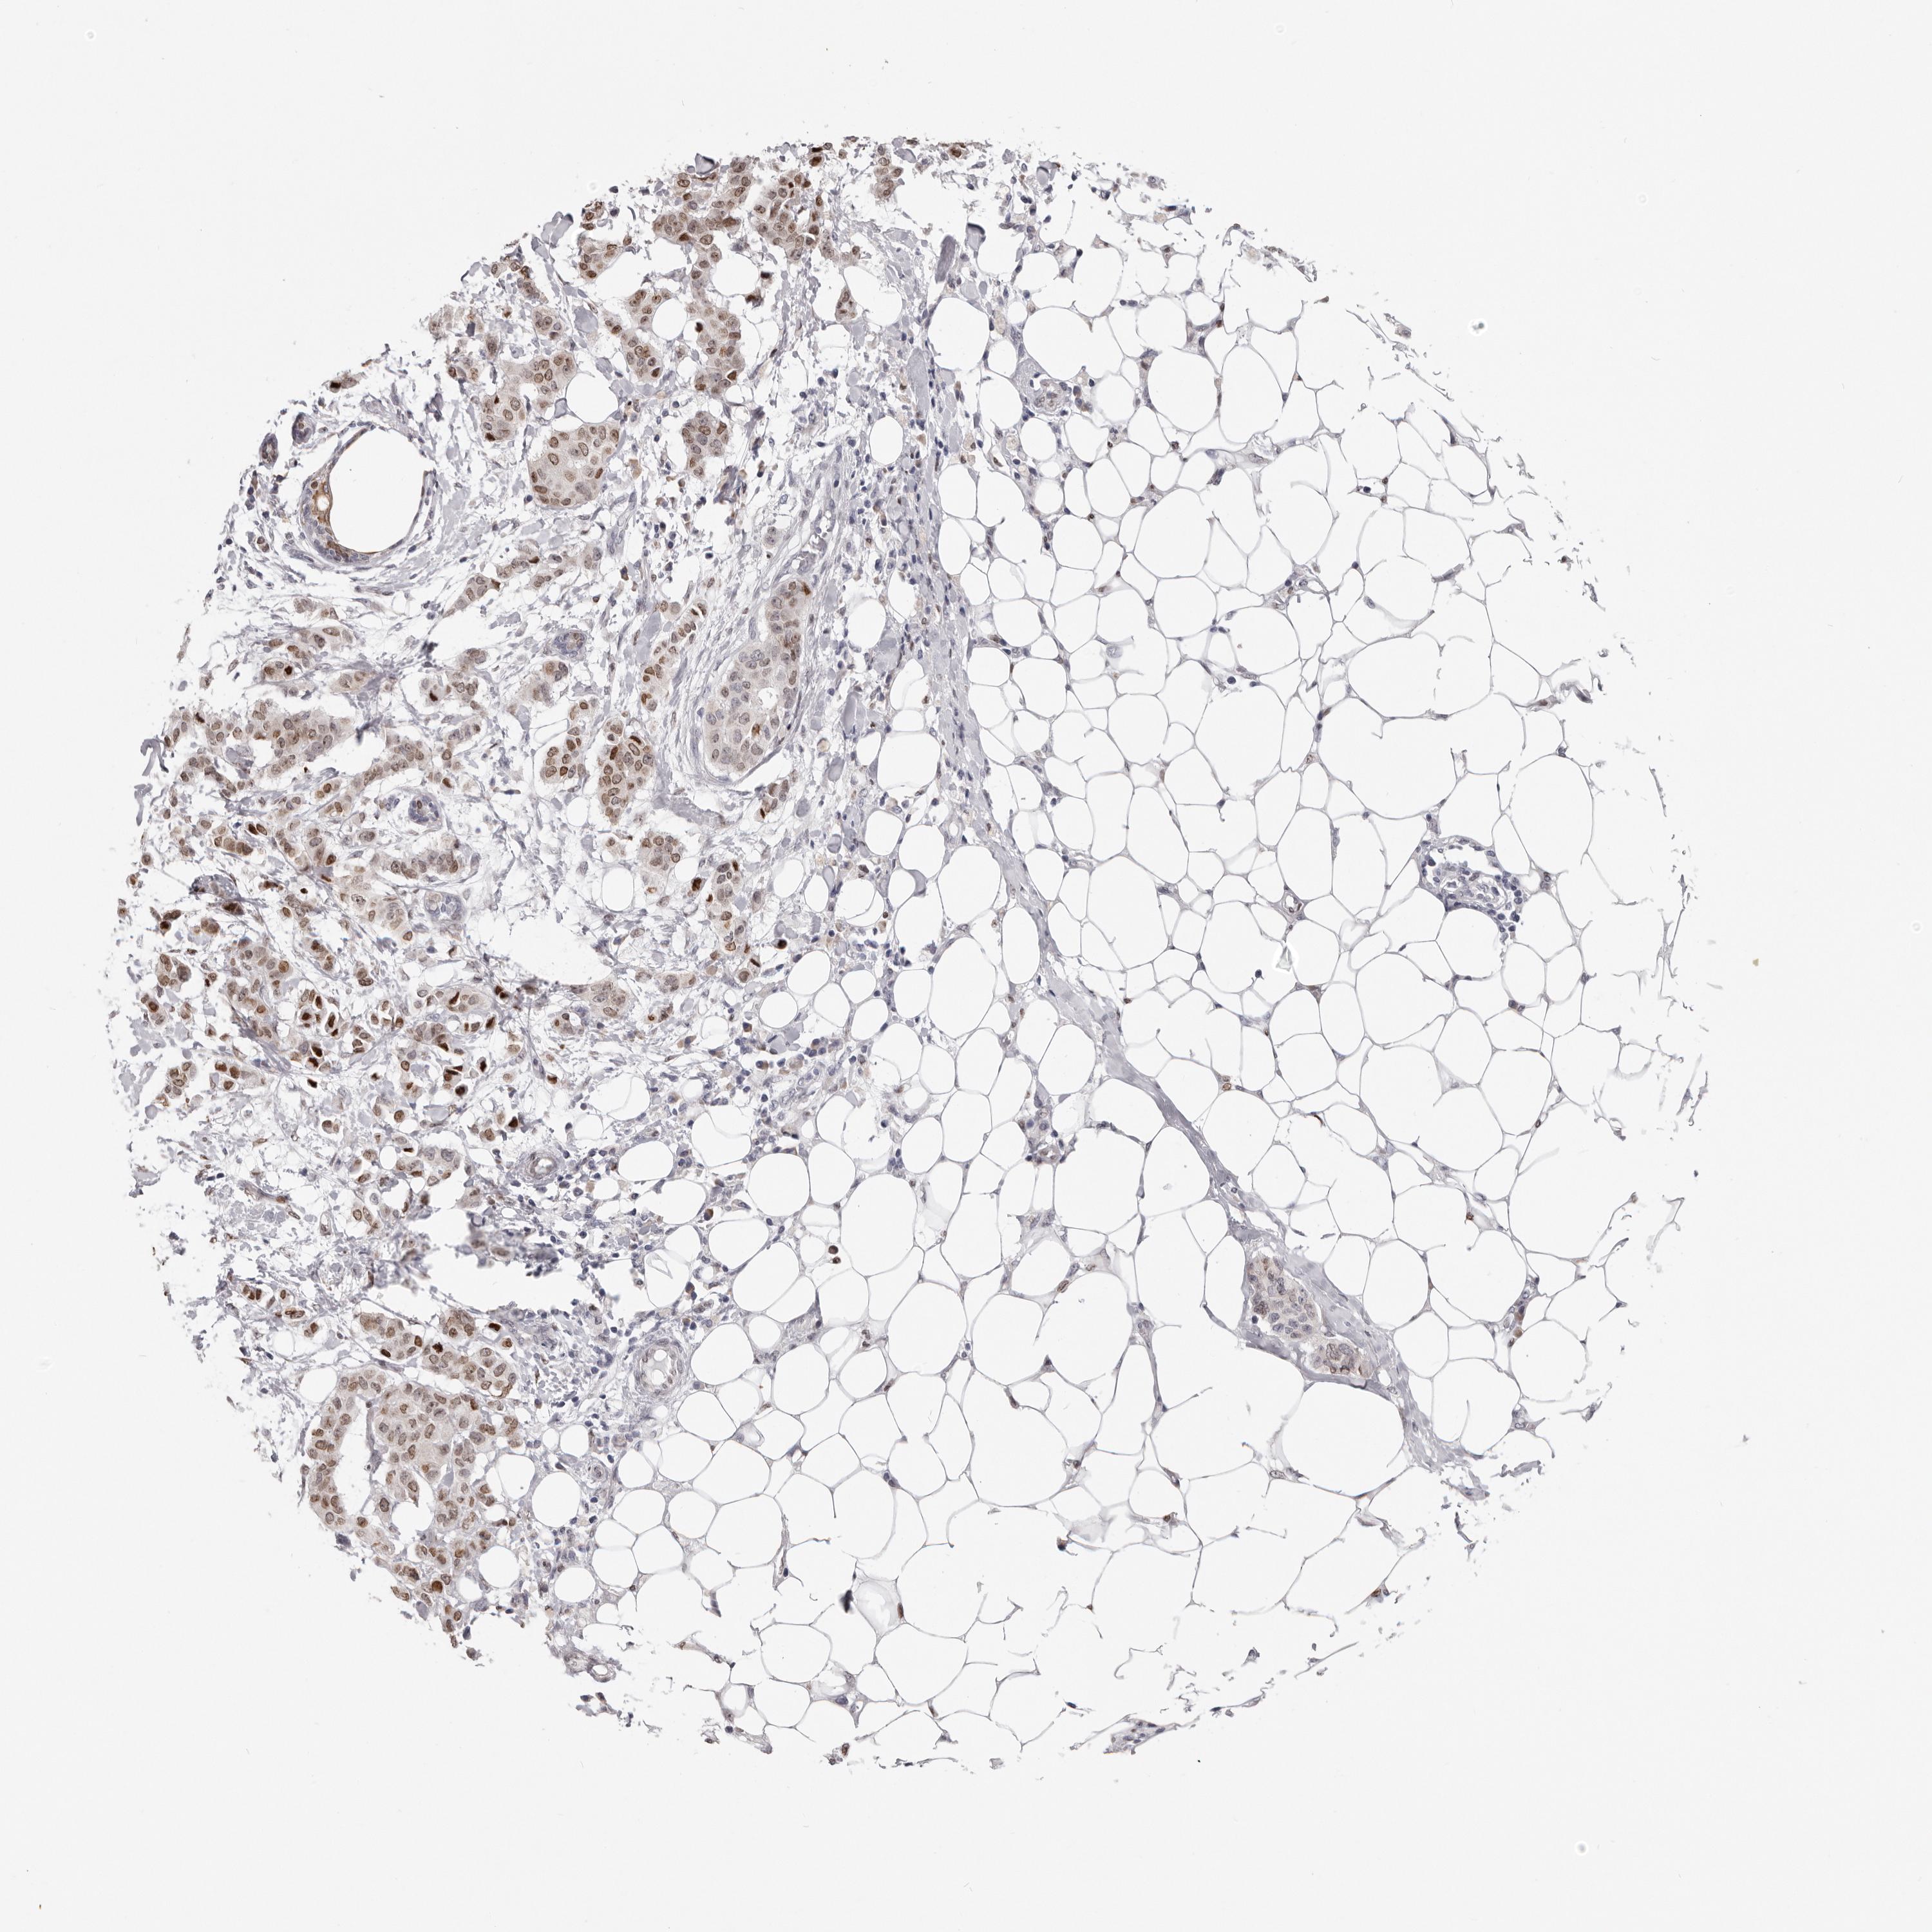

BRCA TCGA BRCA VALIDATION PROTEIN EXPRESSION